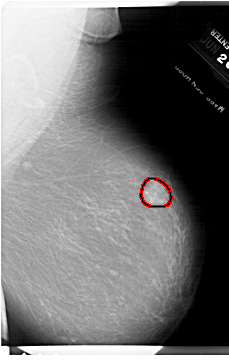

A_1796_1.RIGHT_CC

RIGHT_CC LINES 6841 PIXELS_PER_LINE 4636 BITS_PER_PIXEL 12 RESOLUTION 43.5 OVERLAY

FILE: A_1796_1.RIGHT_CC.OVERLAY

TOTAL_ABNORMALITIES 1

ABNORMALITY 1

LESION_TYPE MASS SHAPE IRREGULAR MARGINS ILL_DEFINED

ASSESSMENT 4

SUBTLETY 5

PATHOLOGY BENIGN

TOTAL_OUTLINES 1

BOUNDARY